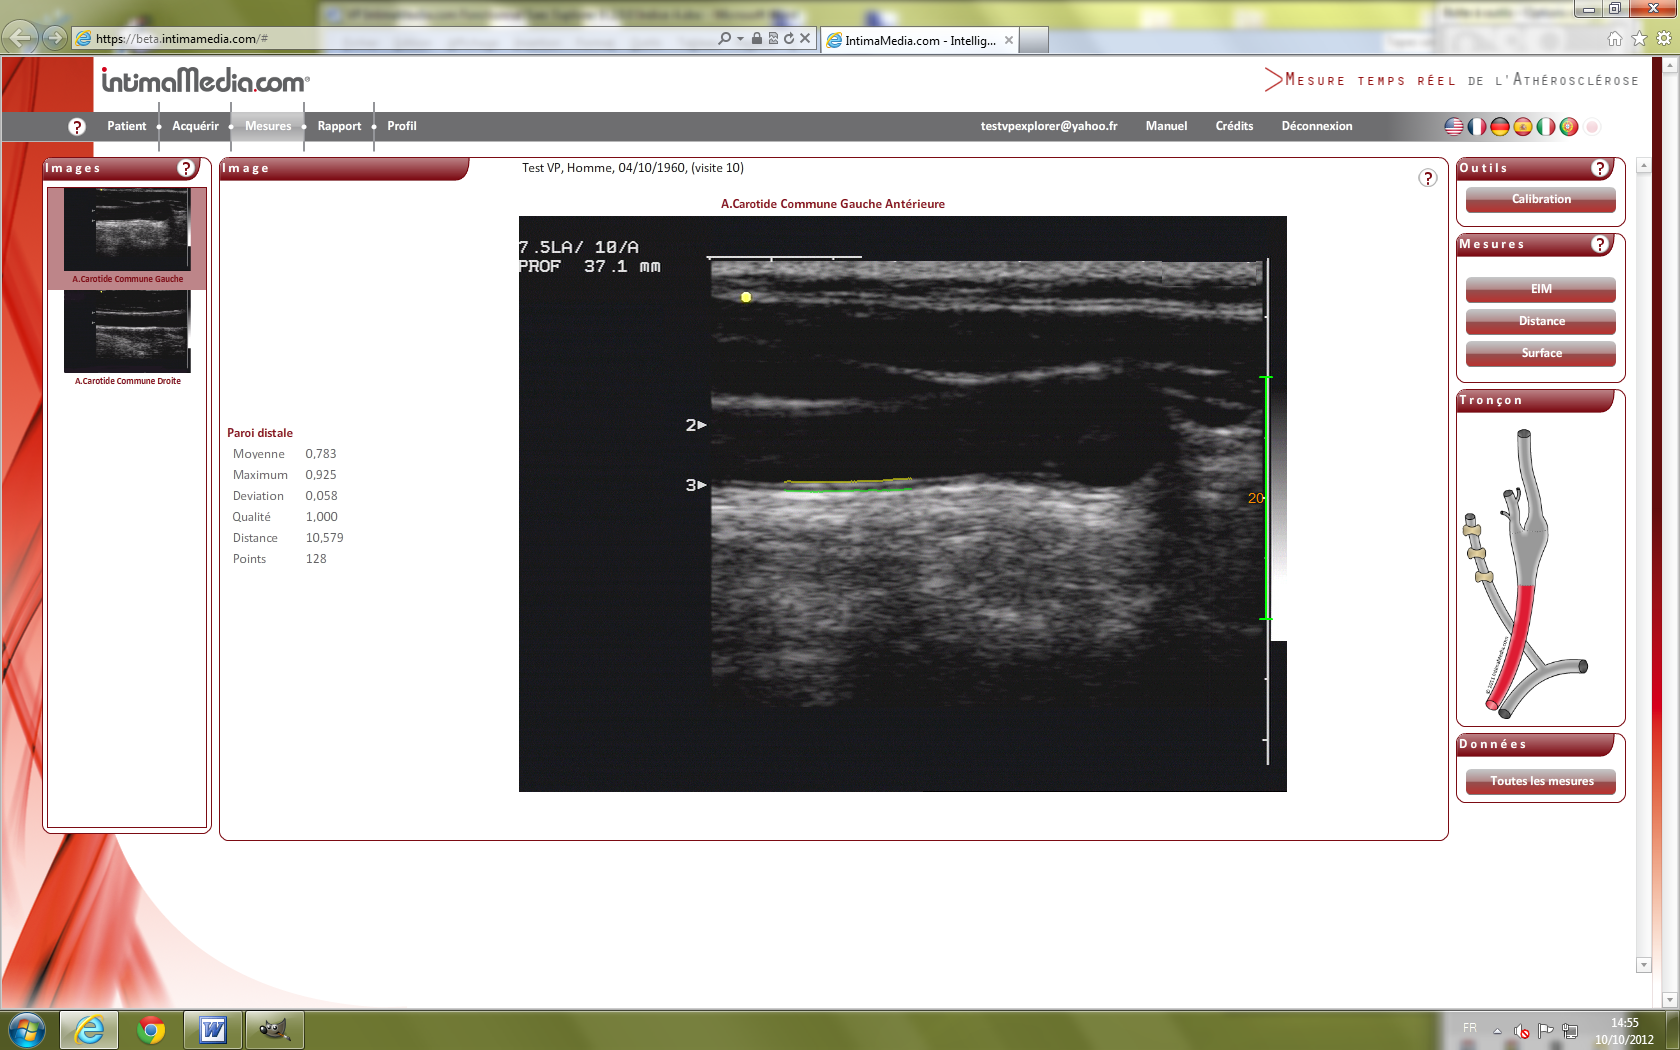

Images VP IExplorer 9. IntimaMedia 2.0.0 Fonctionnal

Test36.png